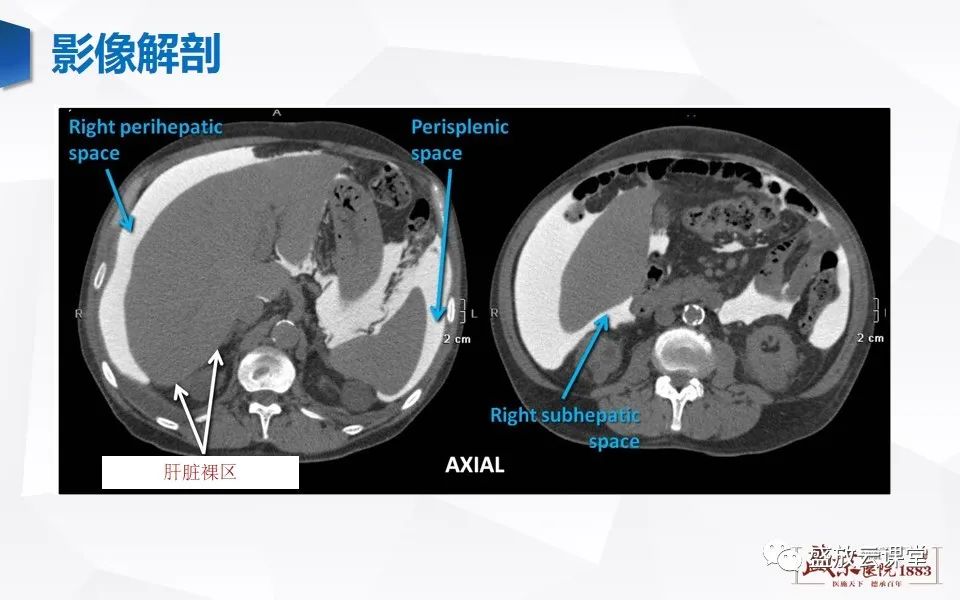

肠系膜解剖及常见病变